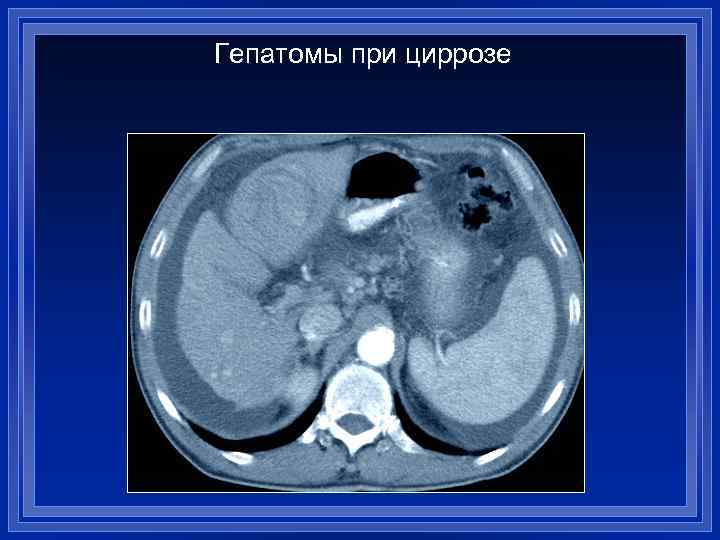

Гепатомы при циррозе